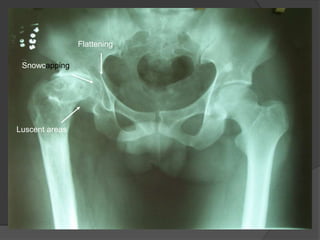

X-ray of head of femur (AVN)

 Crescent Sign

 Snowcapping

 Areas of lucency

 Flattening of joint surface

Snowcapping

Luscent areas

Flattening

X-ray of headof femur (AVN)  Crescent Sign  Snowcapping  Areas of lucency  Flattening of joint surface